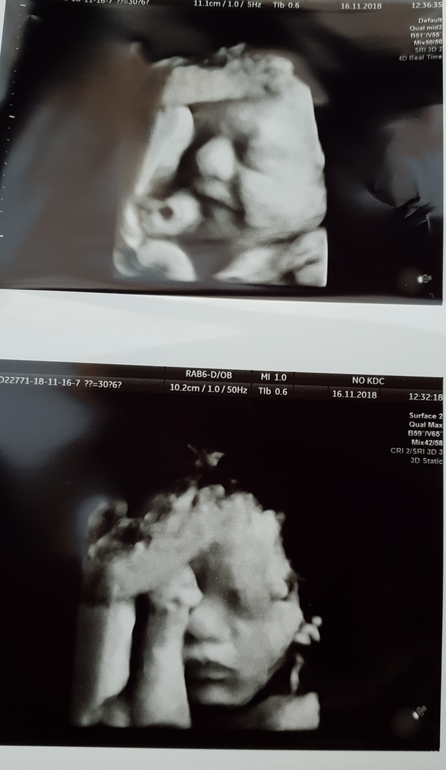

Прошли мы сегодня на 30+2 нед третий скрининг. 🤗

сделали нам фотки - копия папа))) от меня вообще ничего ))))

Из очень плохого: отстаем по весу и по объему живота у малышки на 1,5 недели.

Длинноногая и худая)) видимо отдадим в балет)))🙈🙈🙈